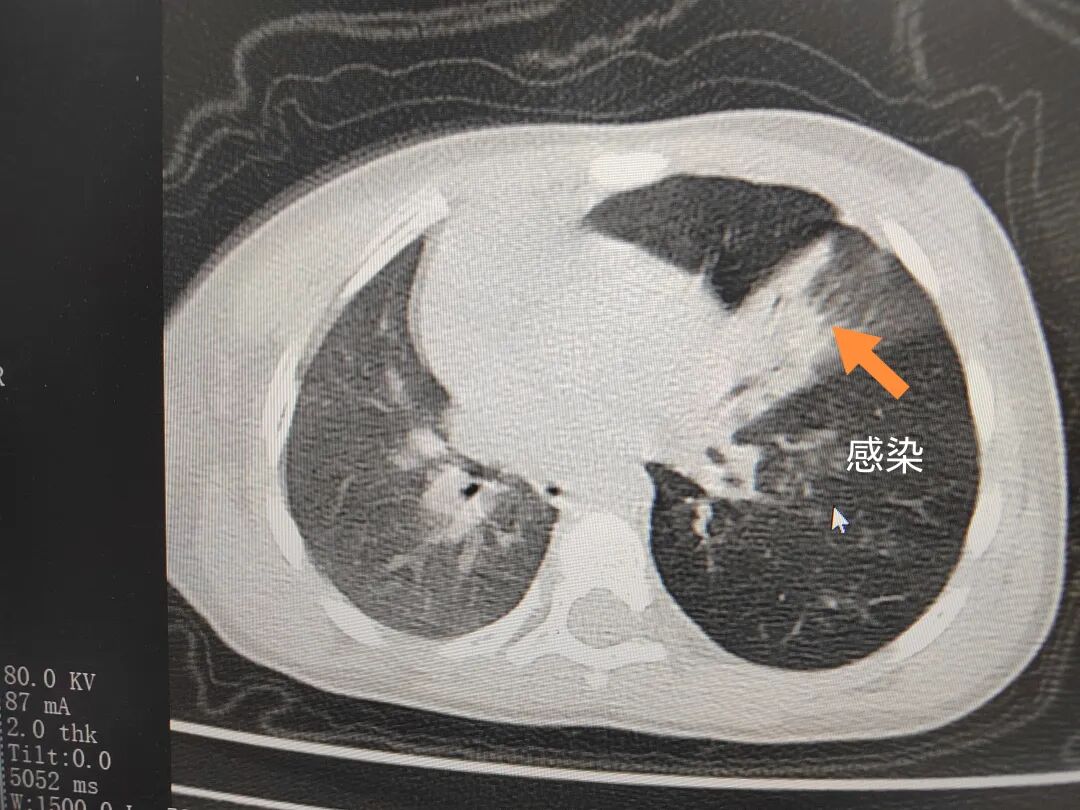

三天后(11月13日),趙寶出現(xiàn)高熱、咳喘加重,家長著急了,再次帶他來到醫(yī)院。CT檢查顯示左肺過度充氣,左肺上下葉支氣管主干見不規(guī)則高密度影,左肺上葉可見大片狀密度增高影,縱隔窗實(shí)變,提示為“左側(cè)支氣管內(nèi)異物并繼發(fā)性改變,左肺上葉舌段肺膨脹不全”。

市二院小兒呼吸內(nèi)科副主任楊亞娟介紹,異物誤入氣道可能導(dǎo)致氣道阻塞,嚴(yán)重時可引發(fā)窒息,甚至危及生命。若異物進(jìn)入支氣管,造成不完全堵塞,可引起阻塞性肺氣腫;如完全堵塞支氣管,則可能導(dǎo)致肺組織萎縮,形成肺不張。此外,若異物存留時間較長,或?yàn)橹参镄援愇铮菀缀喜⒓?xì)菌感染,產(chǎn)生膿性分泌物,進(jìn)而發(fā)展為肺炎。她強(qiáng)調(diào),盡早診斷并取出異物,是減少并發(fā)癥、降低病死率的關(guān)鍵。